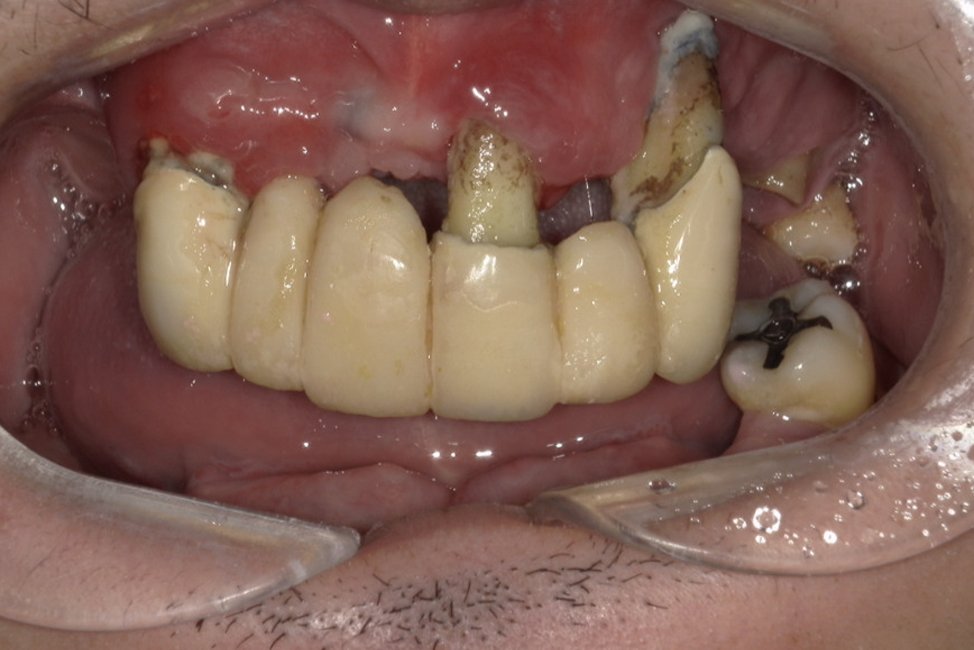

| 主訴 | 全体的にきれいにしたい |

|---|---|

| 治療内容 | 午前中に上下顎共に重度の歯周病、虫歯のため全ての歯を抜歯させていただき下顎はインプラントの土台を3本埋入し歯型を取り午後に上部構造(下顎全ての歯)を装着、上顎は一度総入れ歯を装着させていただきました。 治療が1日で完了しその日のうちに噛めるようになります。 |

| 治療期間 | 2回(1回目に資料取りをさせていただき2回目に下記の全ての治療をさせていただきました。) |

| 治療費 | 250万円 |

| 治療 リスク | 抜歯した部位などに関しては当日痛みが出ますので痛み止めなどを処方させていただきます |